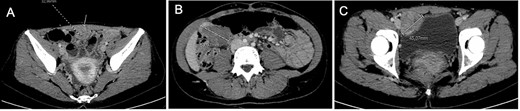

She presented to the emergency department with acute abdominal pain in February 2017. Thoraco–abdomino–pelvic computed tomography (CT) revealed three tissular tumors without evidence of calcification or fat signal adherent to the anterior abdominal wall: one of 34 mm in contact with the infra-umbilical linea alba, another of 44 mm in the right iliac fossa near the bladder and a third of 47 mm in the right hypochondria in contact with the right colic angle (Fig. 1). A transabdominal ultrasound-guided biopsy of the infra-umbilical tumor revealed fusiform cellular proliferation corresponding to smooth muscle-like cells. Based on these findings, the diagnosis of DPL was suspected, and the patient was referred to our center.

Computed tomography at diagnosis showing the three tissular lesions adherent to the anterior abdominal wall. (A) Tumor in contact with infra-umbilical linea alba. (B) Lesion located at the right hypochondria. (C) Tumor situated in the right iliac fossa near the bladder.